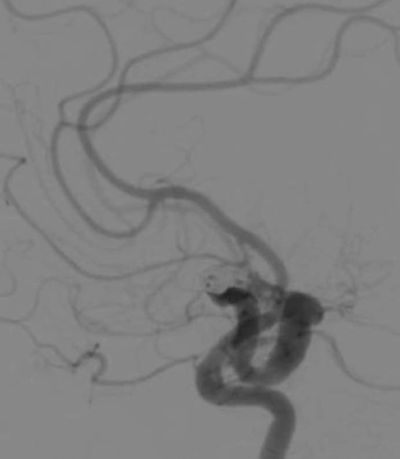

Angiography is a medical imaging technique used to visualize the blood vessels lumen. This is done by injecting a radio-opaque contrast agent, such as Iodine, into the blood vessel via a catheter and imaging using X-ray imaging. This is a diagnosis technique which uses larger x-ray exposures for a very short period of time. We have worked with industry engineers to improve the quality of the images by improving hardware, imaging devices and software. In addition, novel analysis methods were developed to estimate physiological blood flow based only on angiography.

Left/above photo: Digital subtraction angiography (DSA) images acquired with the standard x-ray image intensifier demonstrate no residual filling of the aneurysm.